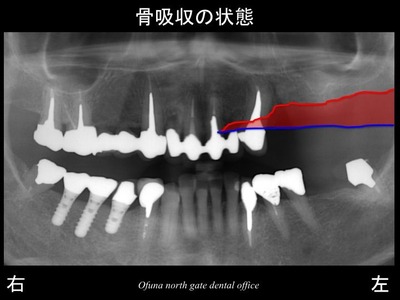

いつものように 骨吸収の状態を分かりやすくするために

骨吸収の状態を線で書いたのが以下のレントゲンになります。

青線が骨吸収を起こす前の骨の位置です。

赤線は、現在の骨の位置です。

かなりの骨吸収が起こっているのが分かるかと思います。